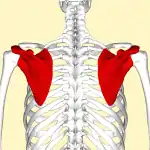

Ceinture scapulaire (anatomie humaine)

La ceinture scapulaire[1] chez l'homme appelée également ceinture pectorale est formée d'un ensemble d'os qui s'articulent entre eux. Elle fait partie du squelette appendiculaire.

Les os de la ceinture scapulaire

Au sens strict du terme la ceinture scapulaire est constituée de quatre os : les deux scapulas et les deux clavicules[3].

Les scapulas sont situées à la partie postéro-supérieure du thorax et les clavicules sont situées en avant, au-dessus de la première côte